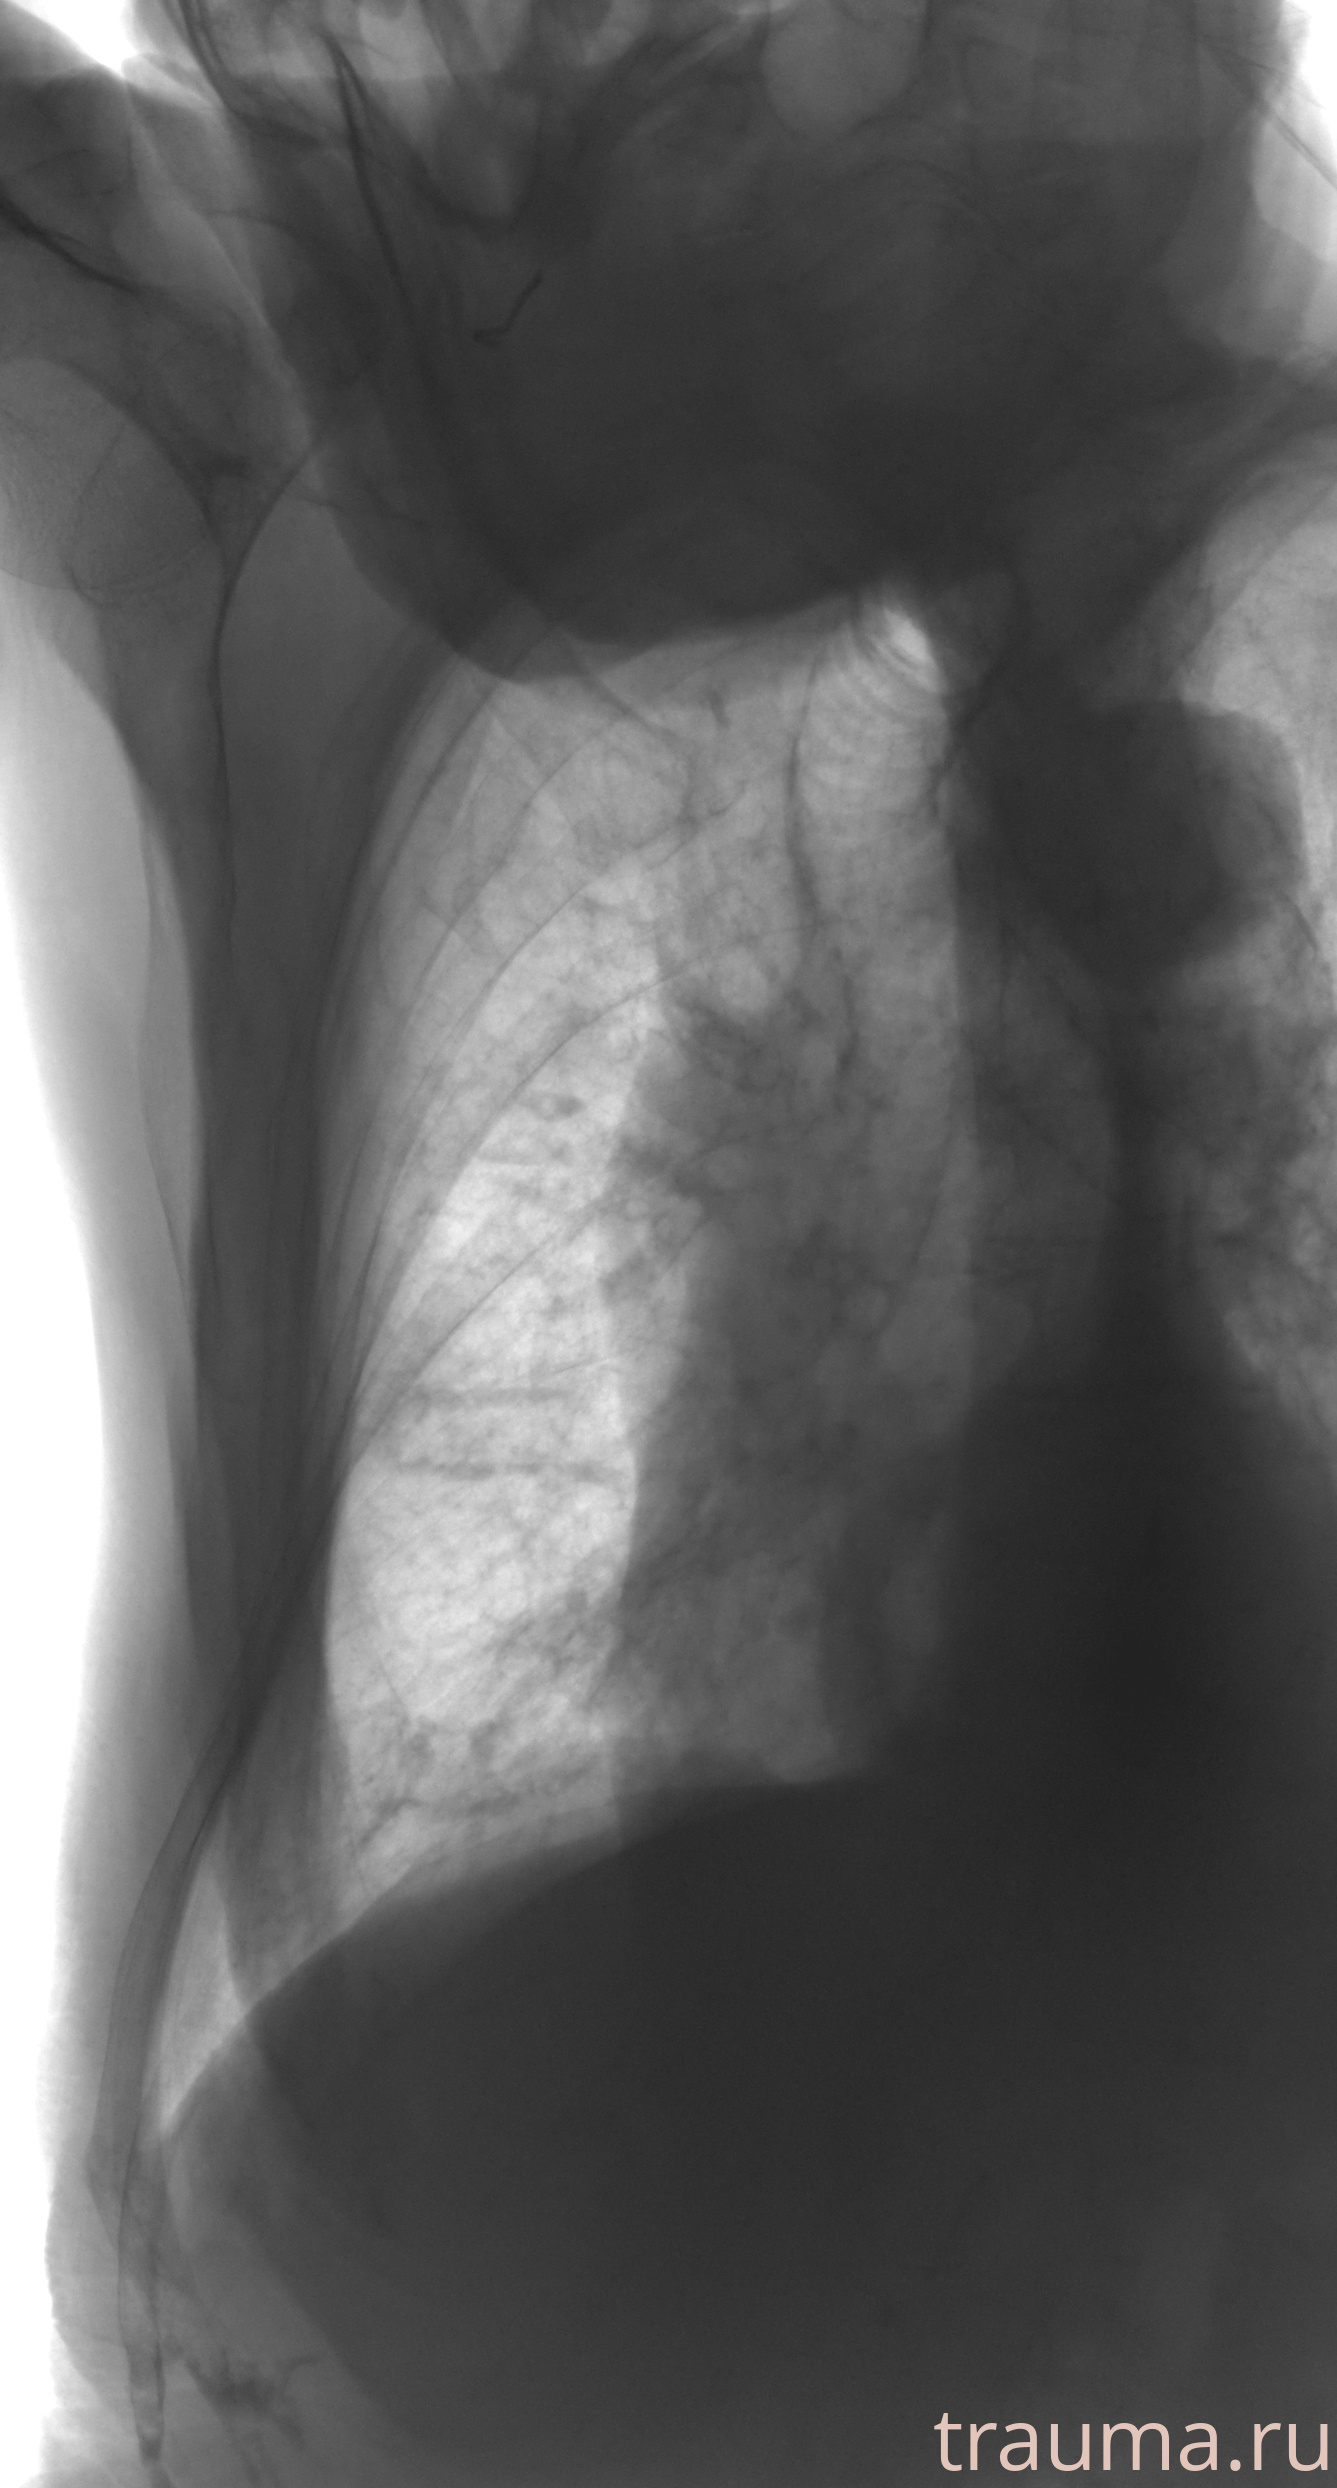

Рентгенограммы

Рентген на дому: по вашему адресу приезжает врач-рентгенолог, травматолог-ортопед с мобильным рентгеновским аппаратом, проводит диагностику травмы или заболевания, делает необходимые рентгенограммы, дает рекомендации по дальнейшему лечению. Получить качественные снимки в домашних условиях возможно благодаря уникальной методике, разработанной МосРентген Центром для института  Склифосовского